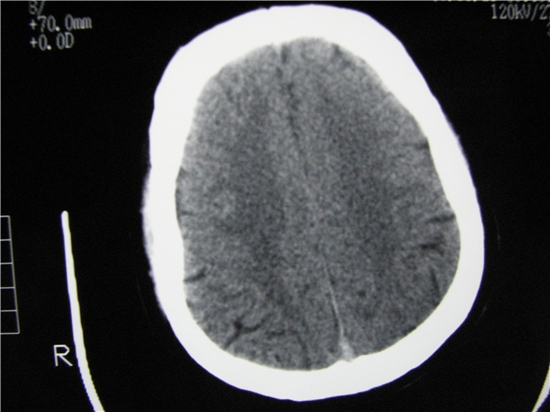

标题: CT23231:男 32岁 车祸伤,鼻腔内出血明显。 [打印本页]

标题: CT23231:男 32岁 车祸伤,鼻腔内出血明显。

左侧额骨、鼻骨骨折,头面部软组织肿胀。

左侧额骨、鼻骨骨折,额窦内的应该是游离骨块